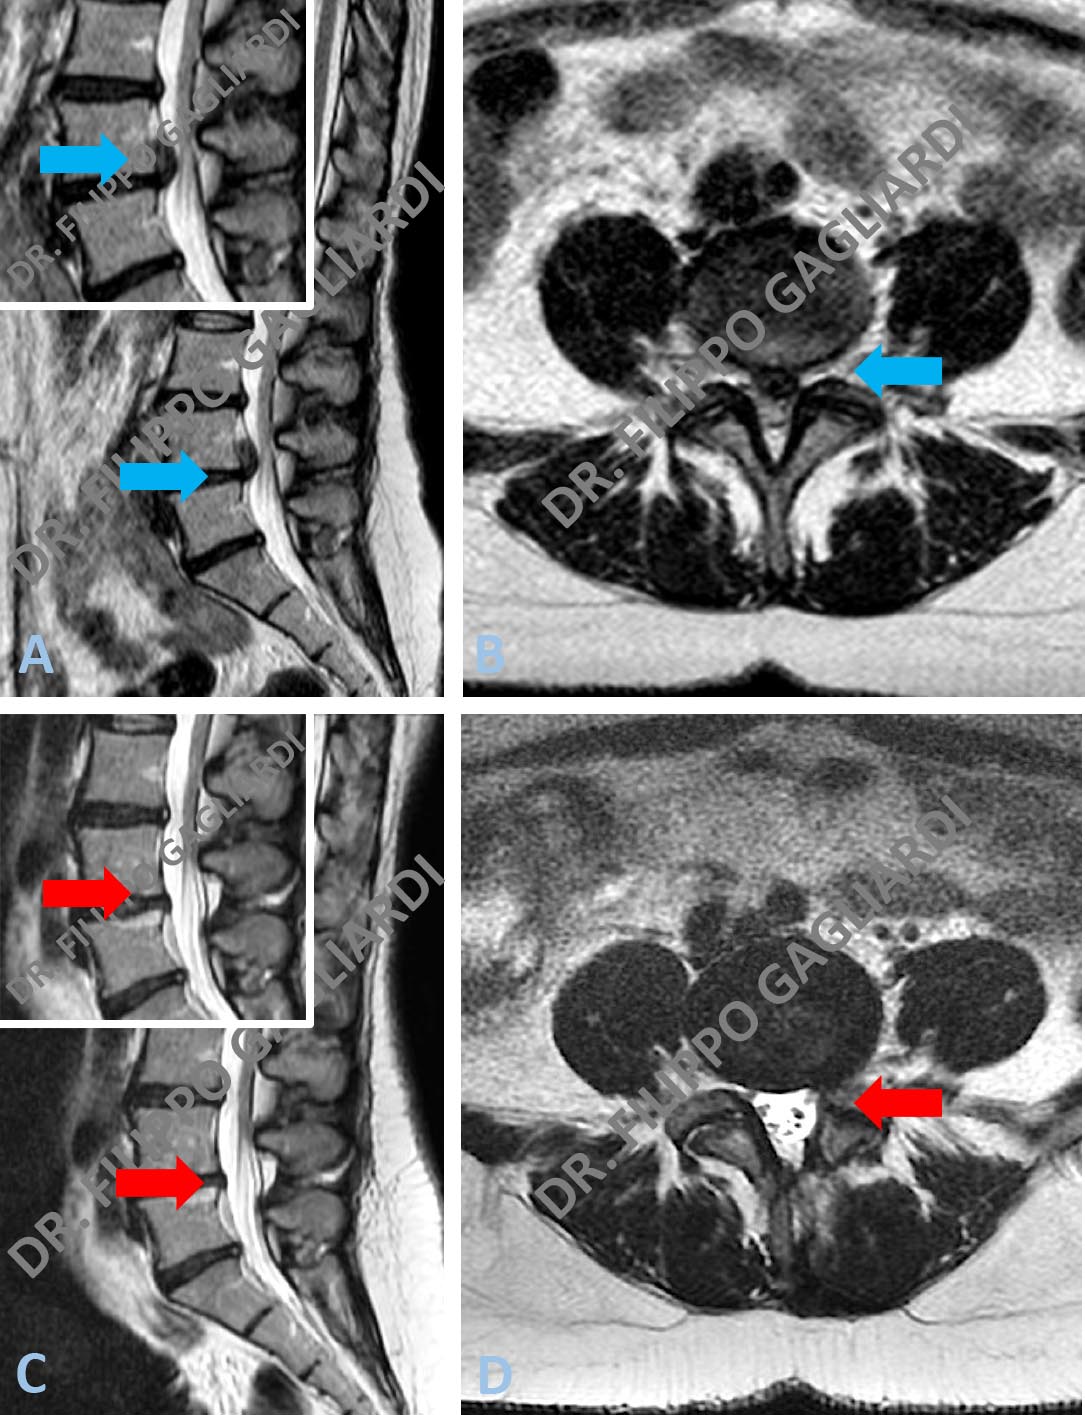

Ernia discale lombare Caso di ernia discale lombare L4-L5 (frecce azzure Figure A e B). ). Il Paziente è stato sottoposto ad intervento di erniectomia. La RM di controllo post operatoria documenta l’asportazione totale dell’ernia e la conseguente decompressione delle radici nervose (frecce rosse Figure C e D).